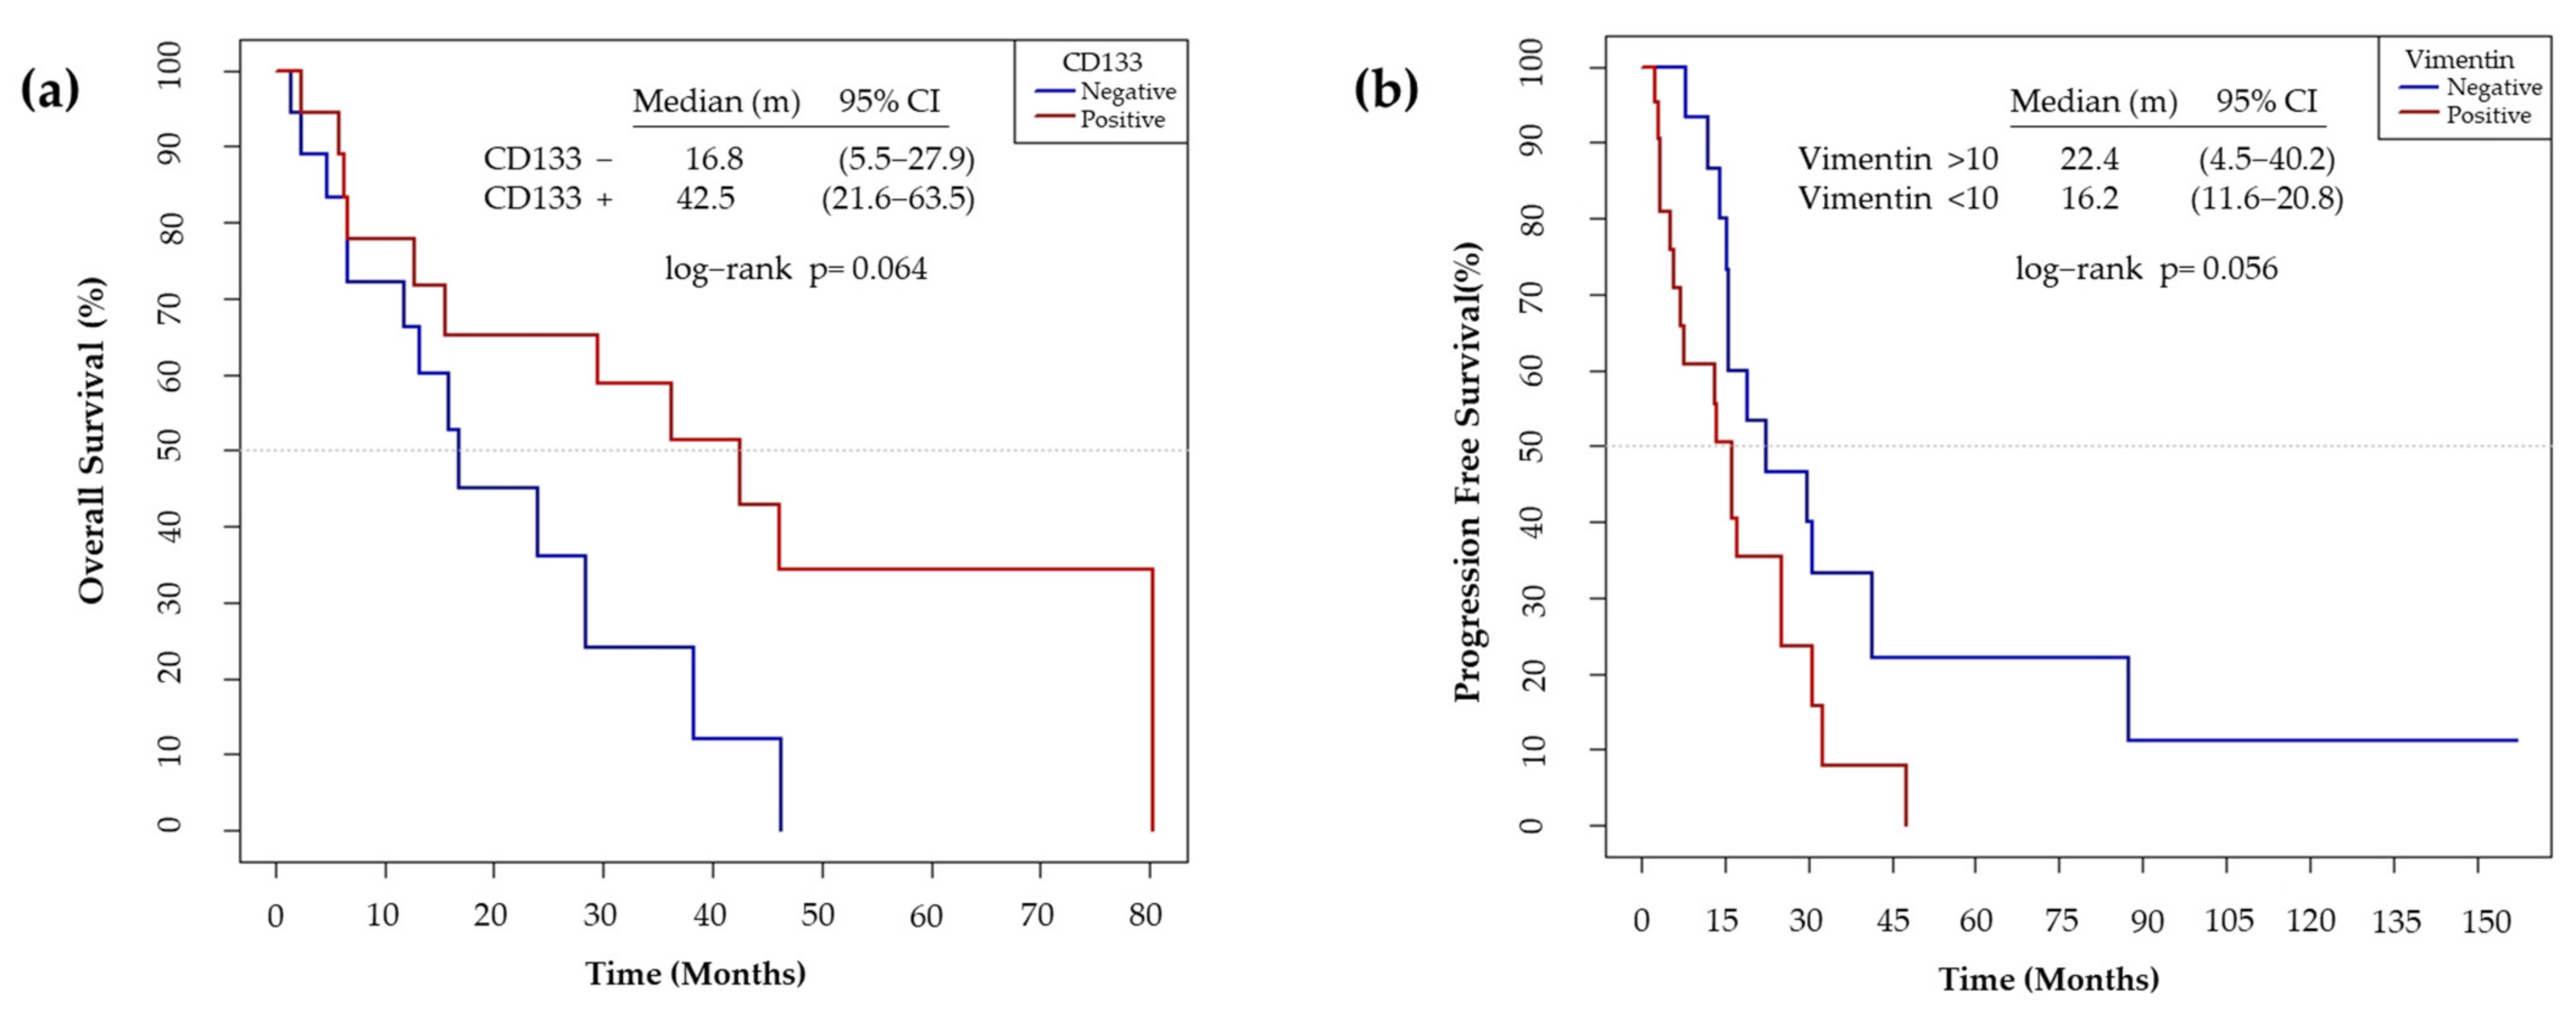

3.6. CD133 and Vimentin Expression in EGFRm NSCLC Patient-Derived Tumors

3.6.2. CD133 and Vimentin Tumor Expression in EGFRm NSCLC Patients